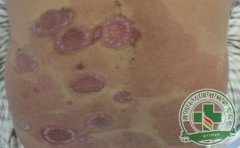

银屑病发病初期症状不明显,首先患者的皮肤会出现点疹,病情发展变成斑块,该病不仅会影响患者的健康,而且对她们的心理也造成诸多伤害,关节型银屑病是比较严重的一种类型,那么,得了关节型银屑病应该如何护理呢?...[详细]